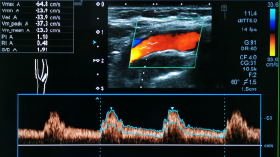

This course provides a comprehensive overview of Doppler ultrasound and hemodynamics, emphasizing the physics, principles, and clinical applications of vascular imaging. Learners will examine Doppler concepts including velocity, frequency shift, waveform analysis, color and spectral Doppler, and the identification of common artifacts. The course also explores normal and pathological blood flow patterns, energy dynamics, and the hemodynamic changes associated with arterial and venous disease, building a foundation for accurate interpretation and optimized vascular sonography.

Ultrasound Doppler Imaging